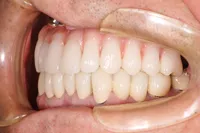

前歯欠損の為来院されたケース

■治療前

■治療後

治療のポイント

- 骨幅が狭い状態です。

- インプラントを埋めると同時に、骨を作る処置をさせて頂きました。

| 主訴 | 上顎の抜歯した箇所の機能障害・審美障害 |

| 治療方法 | 上顎の欠損部位に1本のインプラントを埋入し、同時に外科的治療で骨造成を行った |

| 治療期間 | 約1年 |

| 通院回数等 | 10回 |

| 費用 | 550,000円(税込) |

| リスク・副作用 | 外科的に骨を作る為、治療後に腫れることがある |